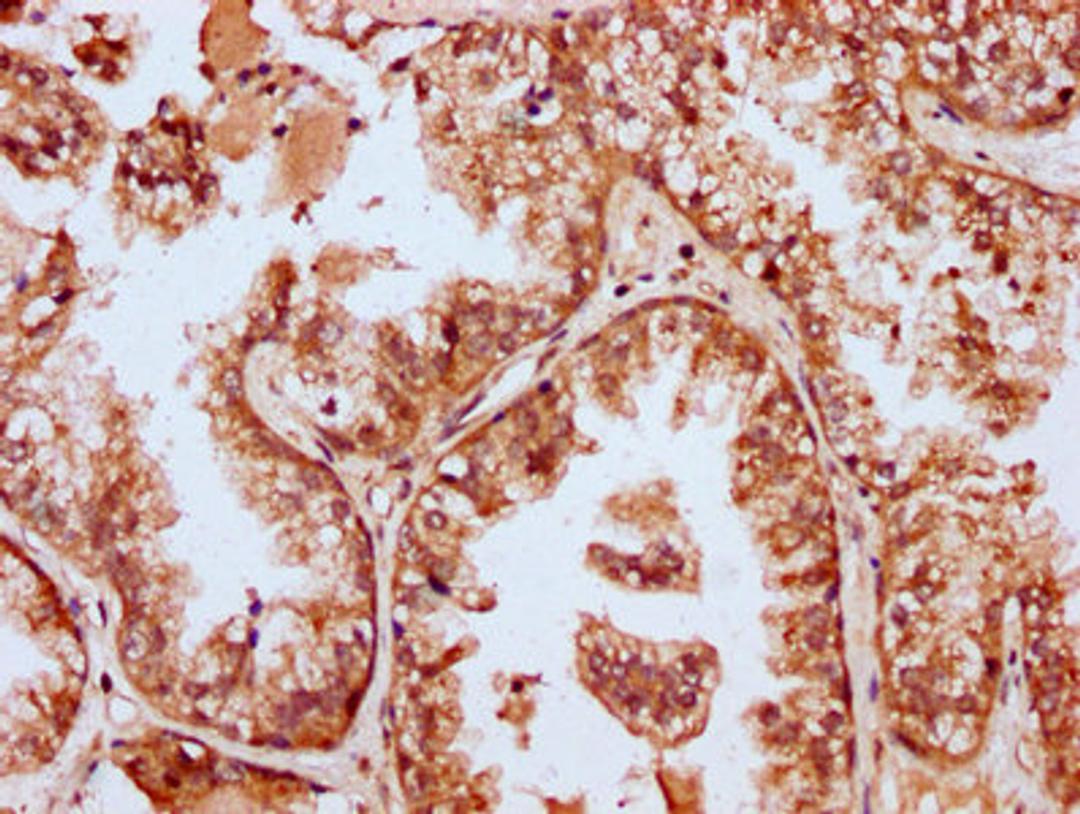

IHC image of CSB-PA868322LA01HU diluted at 1:400 and staining in paraffin-embedded human prostate cancer performed on a Leica BondTM system. After dewaxing and hydration, antigen retrieval was mediated by high pressure in a citrate buffer (pH 6.0). Section was blocked with 10% normal goat serum 30min at RT. Then primary antibody (1% BSA) was incubated at 4°C overnight. The primary is detected by a biotinylated secondary antibody and visualized using an HRP conjugated SP system.